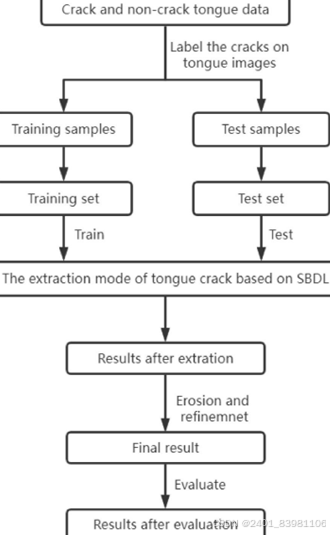

Li et al. 108 提出利用高光谱舌头捕捉舌头图像,然后利用隐马尔可夫模型将舌裂分为12类,该方法在舌头分类方面表现出良好的效果

舌象边缘信息容易丢失 语义分割很难处理舌裂纹 ,精度不高

单独应用深度学习网络SBDL来提取和识别舌头裂缝 ,如图: